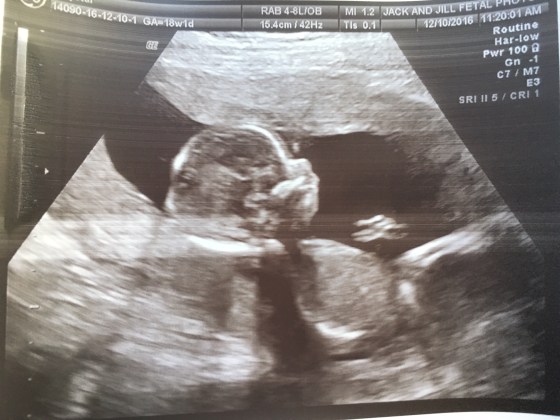

In all seriousness though, the thoughts of excitement flood through, that the reality that a baby is coming is still a dream at this time. It truly is a scary thing that in just 21 more weeks, we will have a bouncy baby girl or boy. That in 21 more weeks, we will have another human to care for, and share our love with, and that in reality our needs are not number 1 any longer. It is a selfless thing to be a parent, and active present parent. I have fears, like any new mother would, but I can say I have no fear for the amount of love I will have for this baby, and the excitement and motivation I will have to create the best little human I can. I have faith that each of us will share a little piece of ourselves with our little one and give a pretty large piece of our hearts to him/her.